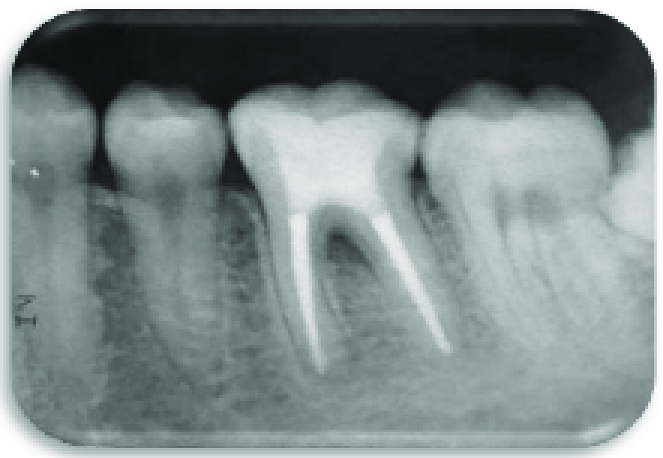

RONTGEN PERIAPICAL

Peripikal adalah jenis radiografi gigi yang dilakukan dengan menempatkan film atau sensor di dalam mulut pasien.

- Saat ada dugaan infeksi atau abses di ujung akar gigi.

- Untuk menilai kerusakan tulang akibat penyakit periodontal.

- Sebelum perawatan saluran akar untuk memeriksa kondisi akar gigi.

- Setelah perawatan endodontik atau operasi gigi untuk memantau hasil.

- Saat ada keluhan nyeri atau ketidaknyamanan pada gigi yang tidak jelas penyebabnya.

- Untuk mendeteksi kelainan gigi seperti gigi impaksi, fraktur akar, atau kista.